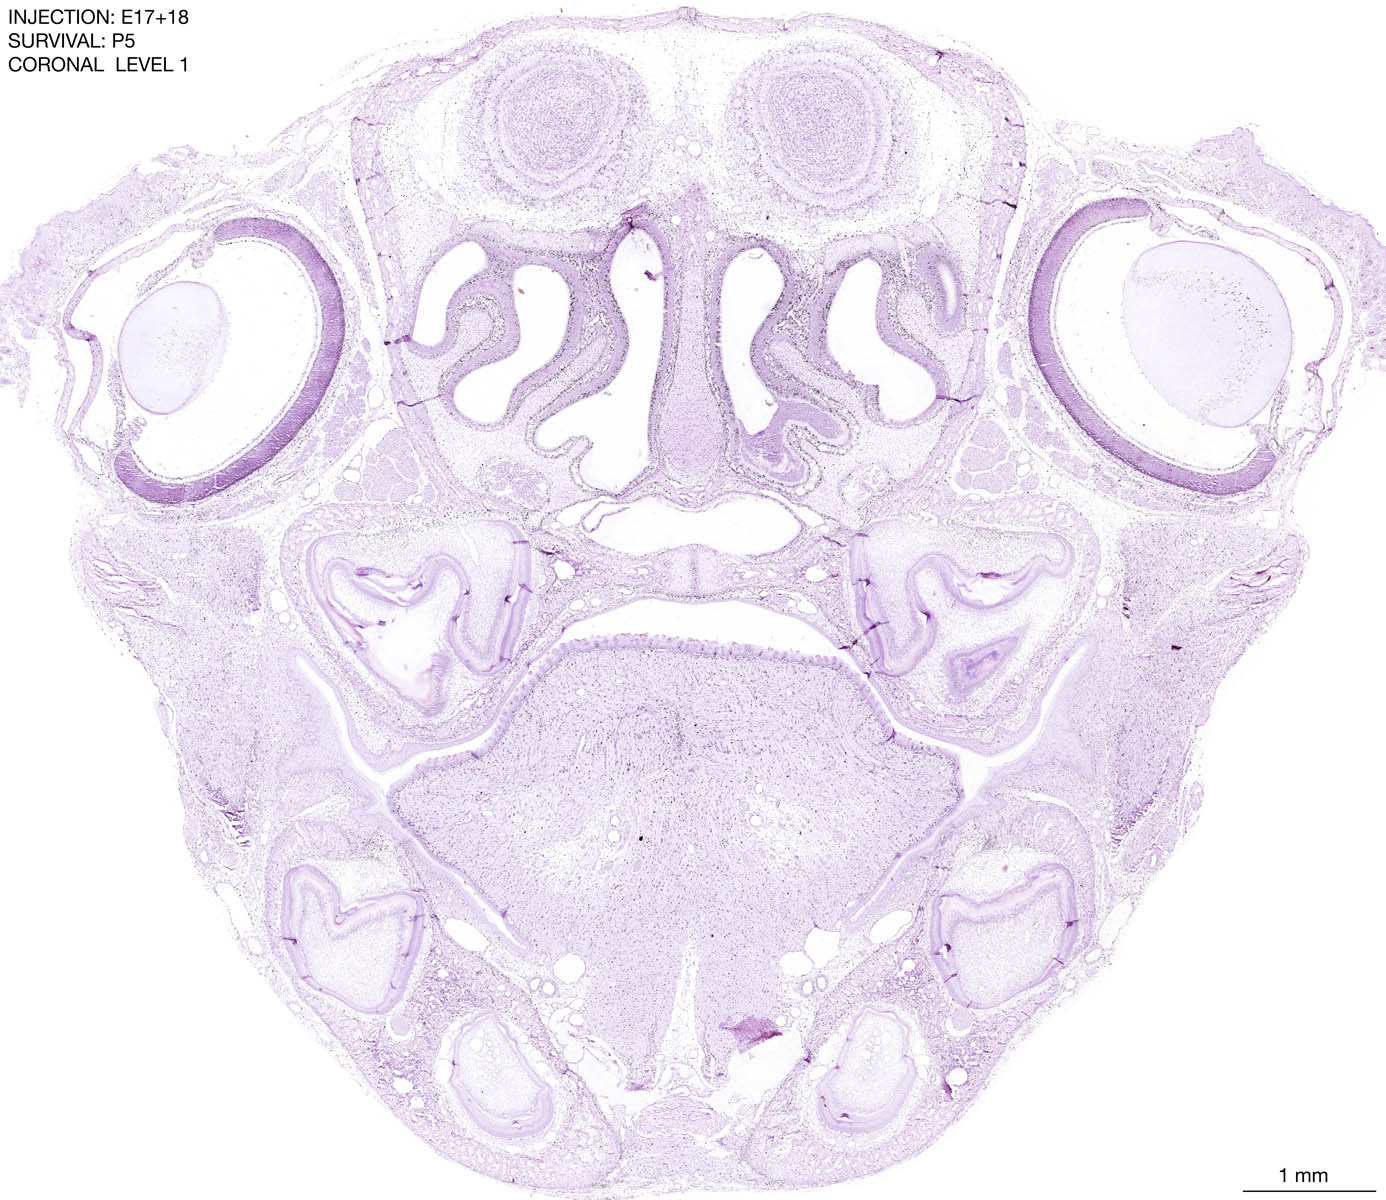

E17+18 P5 Survival The images below are from the brain of a rat that was exposed to tritiated thymidine on E17+18 and survived to P5. Download: Large | High Res Download: Large | High Res Download: Large | High Res Download: Large | High Res Download: Large | High Res Download: Large | High Res Download: Large | High Res Download: Large | High Res Download: Large | High Res Download: Large | High Res Download: Large | High Res Download: Large | High Res Download: Large | High Res Download: Large | High Res Download: Large | High Res Download: Large | High Res Download: Large | High Res Download: Large | High Res Download: Large | High Res Download: Large | High Res Download: Large | High Res Download: Large | High Res Download: Large | High Res Download: Large | High Res Download: Large | High Res Download: Large | High Res